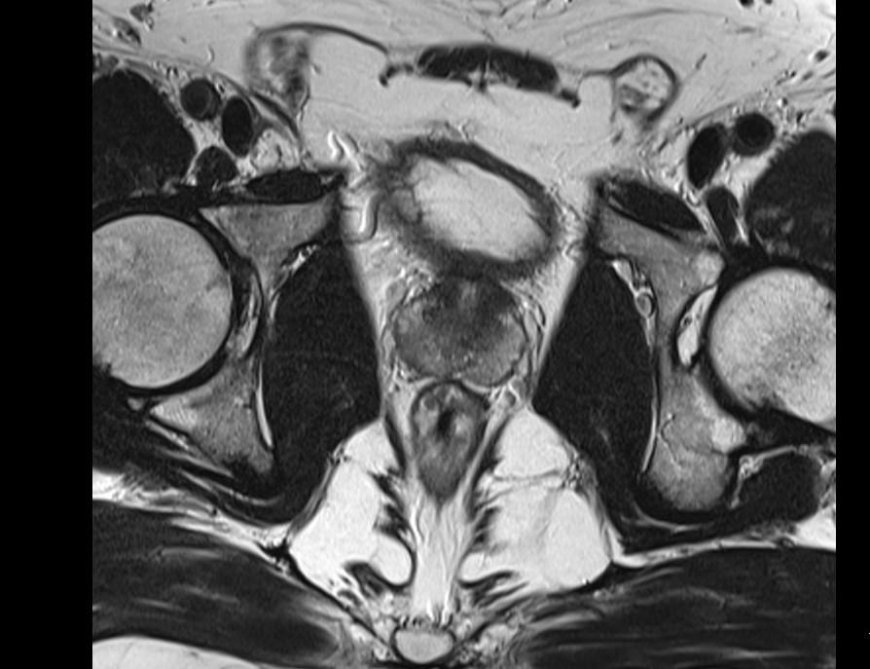

Multiparametrik Prostat MR Nedir?

Multiparametrik Prostat MR, prostatın anatomik ve fonksiyonel özelliklerini aynı anda değerlendiren gelişmiş bir görüntüleme yöntemidir. Üç farklı MR sekansı bir arada uygulanır:

Diffüzyon MR: Hücre yoğunluğunu ölçer. Kanserli dokular yoğun olduğundan düşük ADC değeri gösterir. Gleason skoru ile doğrudan ilişkilidir.

Perfüzyon MR: Doku kanlanmasını inceler. Tümörler, yeni damarlar oluşturdukları için yüksek damarlanma gösterir.

MR Spektroskopi: Hücresel düzeyde kimyasal analiz sağlar. Kanserli dokuda kolin artışı gözlenir.

MR-TRUS Füzyon Biyopsisi: Yeni Nesil Tanı Yöntemi

Geleneksel TRUS biyopsileri körleme yapılırken, MR-TRUS füzyon biyopsisi, MR görüntülerini TRUS ile birleştirerek hedefe yönelik örnekleme sağlar. Bu yöntem, %81 oranında doğru tanı sağlarken, klasik yöntemde bu oran %40’ta kalmaktadır.